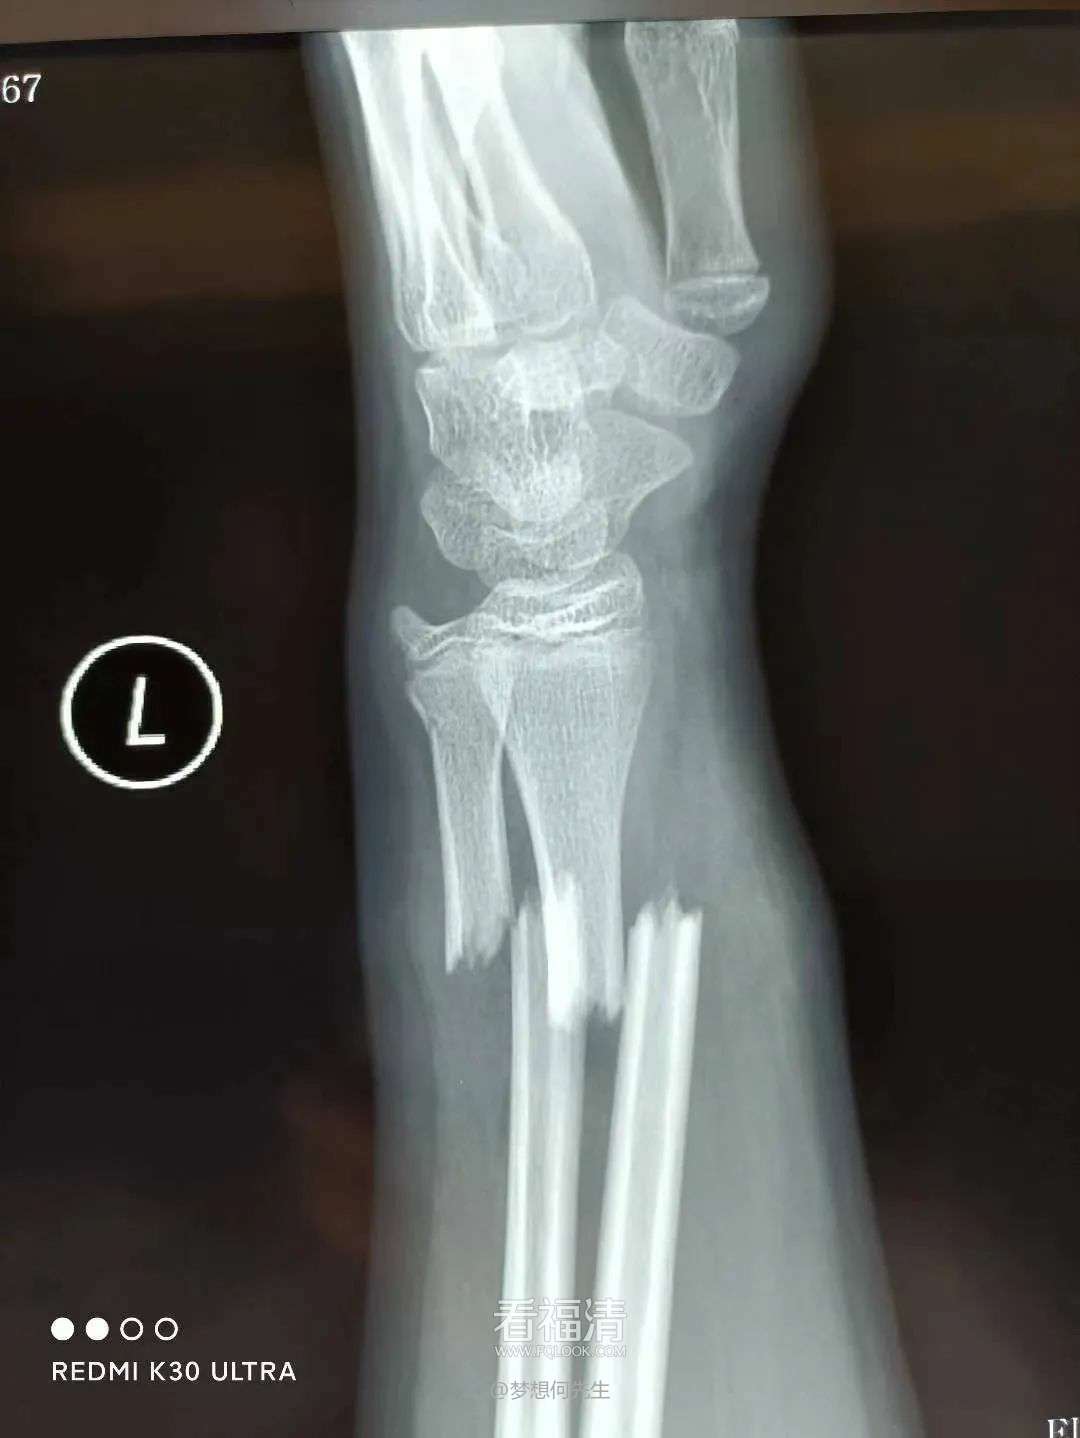

患者39岁,因外伤导致左手疼痛难忍,前来福清市第五医院中医骨科门诊寻求治疗。经过详细检查,患者被确诊为左侧桡骨远端粉碎性骨折伴下尺桡关节脱位。接诊的王征勇运用精湛的正骨手法进行复位,并在中医正骨理论的指导下,使用石膏进行固定。这种治疗方案有效地稳定了复位后的桡骨远端骨折,促进了骨折的愈合,避免了不必要的手术治疗,同时显著减轻了患者的疼痛感。

复位前

复位后